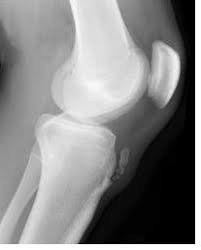

Knee disease osgood schlatters in adults. In four cases a true joint had formed between an ossicle in the patellar ligament and a facet on the tibia. Osgood-Schlatter disease is a painful condition causing inflammation just below the knee. The tendon below your kneecap called the patellar tendon attaches to the tibial tuberosity on the shinbone called the tibia.

Symptoms of Osgood-Schlatter in Adults While Osgood-Schlatter may occur to adults it usually only affects one knee and is not very painful. Osgood Schlatter disease also known as osteochondrosis or traction apophysitis of the tibial tubercle is a common cause of anterior knee pain in the skeletally immature athletic population. Friday April 05 2019.

Osgood Schlatter disease or Osgood Schlatter lesion is a very common cause of knee pain in children between the ages of 10 and 15 years old. An adhesive tape is placed across the part of the bone that is tender and swollen the tibial tuberosity while the patients knee is bent. Osgood-Schlatter is a common disease with most cases resolving spontaneously with skeletal maturity.